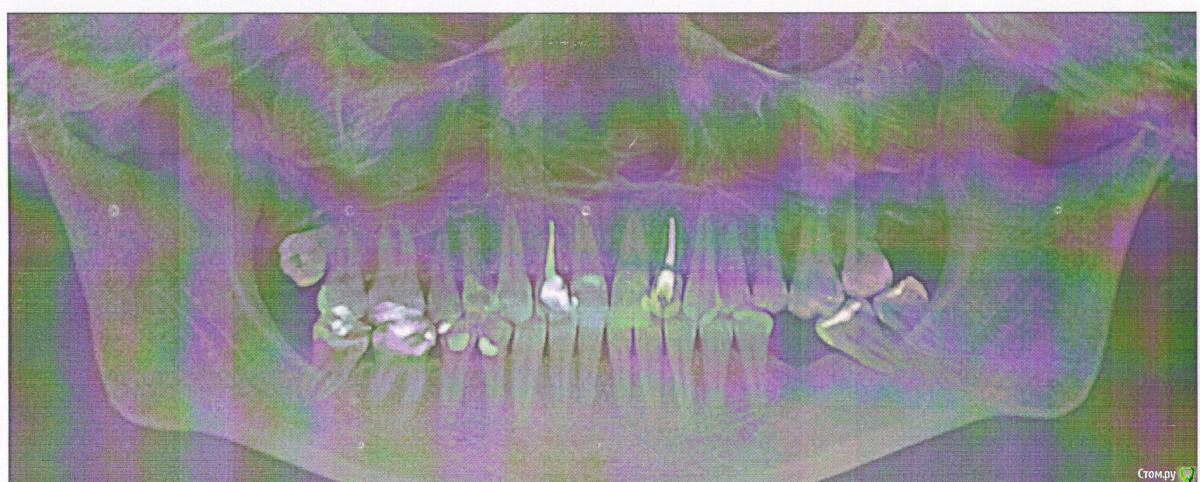

Scrabble Опубликовано 26 апреля, 2015 Поделиться Опубликовано 26 апреля, 2015 (изменено) Конечно, 11 зуб болит-там помимо маленькой пломбы(кстати, с нарушенным краевым прилеганием) есть ещё и маленькая пломба у шейки зуба. То, что Вы описываете, совершенно классически укладывается в схему пульпита, плавно перетекающего в периодонтит. Боли от горячего-пульпа была на последнем издыхании, а потом погибла. На р-ме картину периодонтита искать сейчас не надо-он пока в свежей острой стадии. Сделайте эндо-и всё пройдёт. Изменено 26 апреля, 2015 пользователем Scrabble Ссылка на комментарий

Liso4ka Опубликовано 27 апреля, 2015 Автор Поделиться Опубликовано 27 апреля, 2015 Конечно, 11 зуб болит-там помимо маленькой пломбы(кстати, с нарушенным краевым прилеганием) есть ещё и маленькая пломба у шейки зуба. То, что Вы описываете, совершенно классически укладывается в схему пульпита, плавно перетекающего в периодонтит. Боли от горячего-пульпа была на последнем издыхании, а потом погибла. На р-ме картину периодонтита искать сейчас не надо-он пока в свежей острой стадии. Сделайте эндо-и всё пройдёт.спасибо большое за ответ. Хотела уточнить - мы про один и тот же зуб говорим? у меня болит зуб 21 - верхняя левая 1ка, на той стороне, где удалена 6ка. А Вы мне вроде как описали про зуб 11 (просто, может, на ОПГ не понятно где левая сторона , а где правая) - там у меня на 11 действительно пломбочка спереди стоит ближе к шейке - был дефект эмали , борозда на эмали появилась горизонтальная). И еще вопрос - то есть пульпа погибла, прошла реакция на горячее, сейчас ослабевает реакция на прикусывание. Она может потом вообще пройти и периодонтит перейти в хронический? То есть даже если боли пройдут, то все равно надо депульпировать? Эндо - это же Вы имели ввиду депульпирование? И еще вопросик - если пломба с нарушенным краевым прилеганием- то ее тоже надо переделывать?спасибо заранее Вам! Ссылка на комментарий